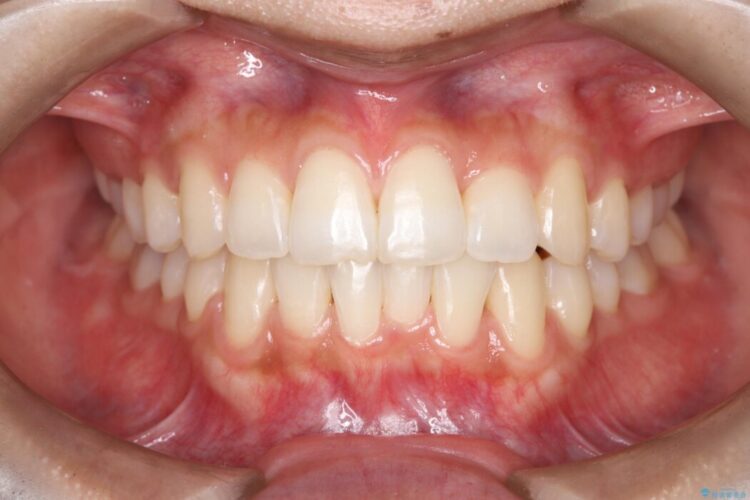

歯の移動量や力のコントロールを最適化することで、短期間で治療完了しました。

「矯正は時間がかかる」というイメージをお持ちの方も多いですが、症例によっては、非抜歯でも短期間で改善が可能な場合があります。

治療後は歯並び・かみ合わせともに大きく改善し、患者様にも大変ご満足いただけました。